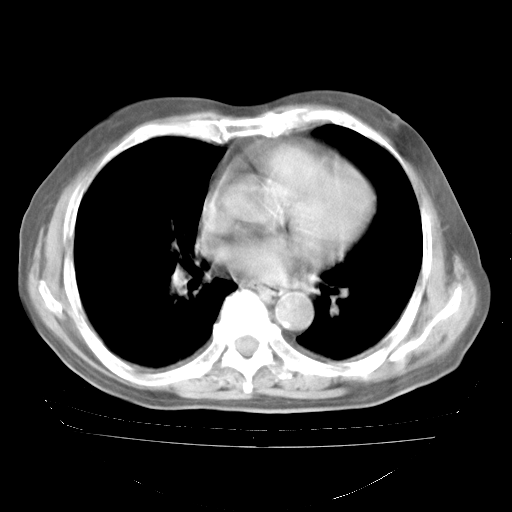

4月28日肺部CT

个人阅读4.14日肺部CT平扫:纵隔窗无异常,但肺窗示:双下肺内、后基底段有片絮状侵润影,部位以后基底段为著,以间质改变为主,呈急性肺泡炎征像,和首次住院影像学有相似之处。仅是个人读片,明日请相关专家再读片哈。其它建议同上。

1、108#的是4月14日的胸部CT(发此贴时还没看着28日的CT)。14日的胸部CT其实已经出现改变(如108#所述),个人认为28日的胸部CT除纵膈窗疑似有双侧胸膜增厚或少量胸积液(可行胸部B超明确)外,与4月14日对照病变有所加重;2、已经给予“异烟肼、利福平、乙胺丁醇”抗痨治疗?如果是,甲强龙80mg可缓慢减量;如果环磷酰胺已停用,暂不使用;3、中性粒细胞92%,明显升高,目前体温情况?注意合并细菌感染可能,使用左氧氟沙星情况下,是否联用B-内酰胺类抗菌药物?另外是查免疫全套非风湿全套。

今请临免主任会诊后认为:4月14日胸部CT已有双下肺间质性改变。患者病情复发多系激素减量过快不正规所致。目前甲强龙80mg/日,一周后酌情开始减量,不易过快。环磷酰胺若已停用,暂不使用。他同意目前抗菌药物使用,但应考虑是否加用B-内酰胺类抗菌药物(中性细胞明显增高);2、结核复发目前依据不足;3、若免疫全套各项指标正常,考虑多系特发性肺间质炎可能大。4、加强支持,并注意保护胃黏膜。